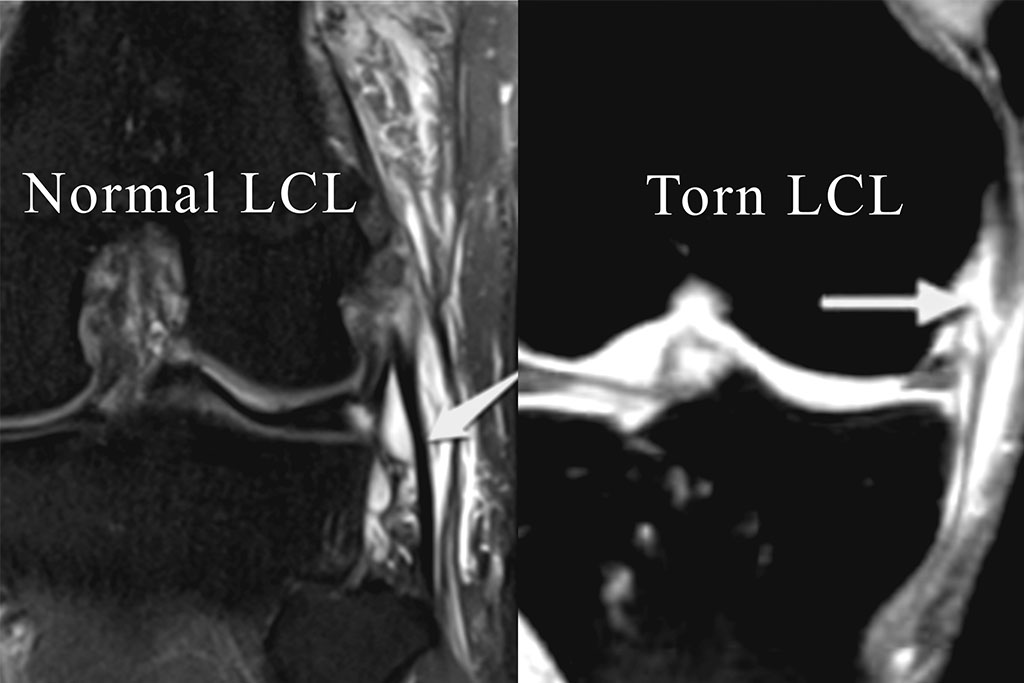

Ligament (ACL) Tear

The anterior cruciate ligament (ACL) is one of the main... read more